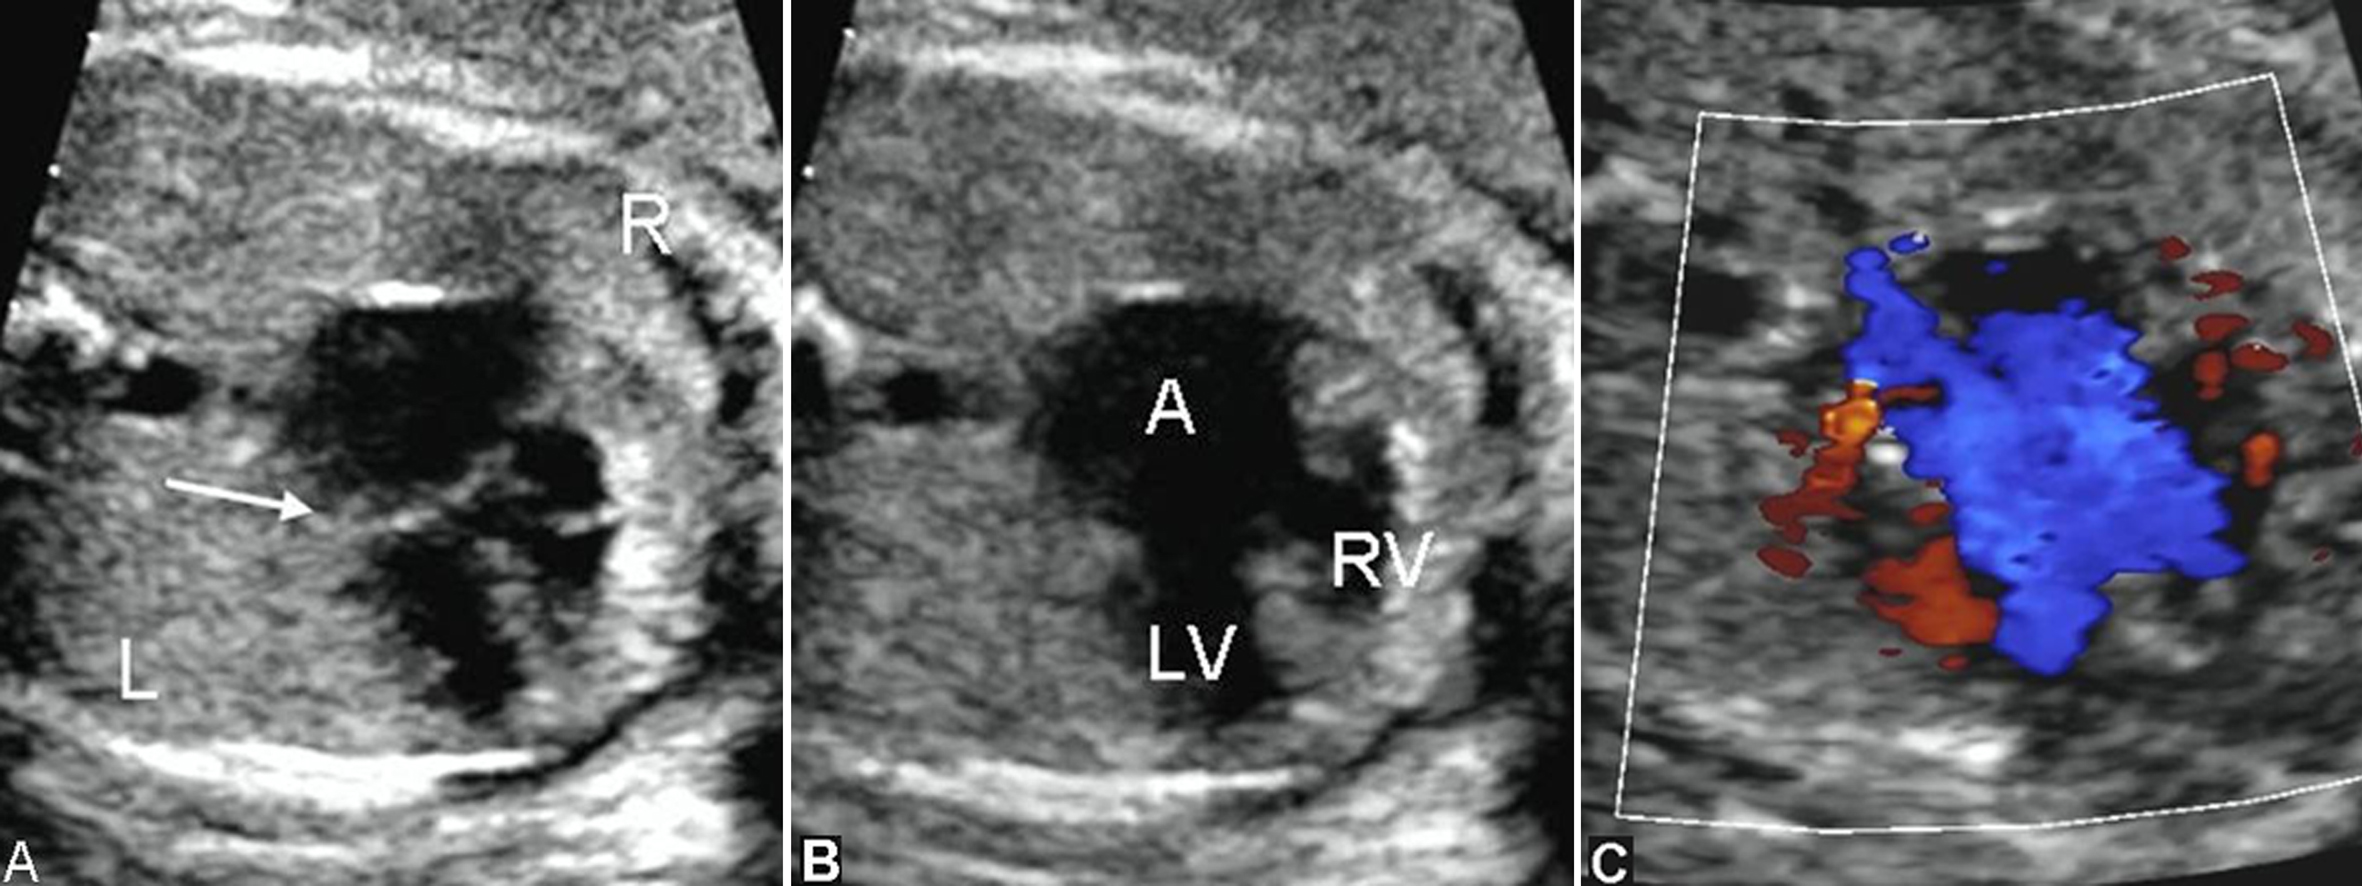

部分性AVSD超声图像特征为:房间隔的原发隔缺失,房室瓣与房室隔十字相交的正常结构消失,二、三尖瓣关闭时呈水平位,同时伴有二尖瓣和(或)三尖瓣反流,而室间隔完整,心室水平无分流(图3)。原发孔型ASD应与增大的冠状静脉窦相鉴别。前者心尖四腔切面观始终无法显示正常的十字交叉结构,后者声束在心尖四腔切面观靠后时显示等号状增大的冠状静脉窦,同时不能显示二尖瓣,而心尖四腔切面观时可见正常的十字交叉结构,并可见左侧房室沟处呈环状增大的冠状静脉窦(图4);另外,冠状静脉窦增宽常合并左侧上腔静脉永存,三血管气管切面在肺动脉左侧可见与右侧上腔静脉对称的血管即左侧上腔静脉(图5)。

完全性AVSD超声图像特征为:四腔心切面观房室瓣与房室隔十字相交的正常结构消失,房间隔下部分及室间隔流入道部分缺失;彩色多普勒检查时两条平行的房室血流消失,呈H型血流(图6)。共同房室瓣一般由五个瓣组成,常伴有房室瓣膜功能不良和关闭不全。

图4 胎儿冠状静脉窦增宽